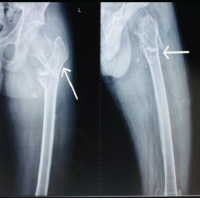

The tibia, talus, and calcaneus were carefully aligned to maximize bone contact and create a plantigrade foot. The hindfoot was positioned at 0° dorsiflexion, 5° heel valgus, and 5–10° external rotation. After debriding both articular surfaces, a guidewire was inserted as shown in (Fig. 4) through the subtalar and tibiotalar joints under arthroscopic guidance. Once the intramedullary reaming was completed, the appropriately sized retrograde nail was inserted, and confirmed under the image intensifier as shown in (Fig. 5). The proximal screw was inserted first followed by a talar screw and at last calcaneo-cuboid screw with compression device was inserted. Following the procedure, the ankle was stabilized in a below-knee plaster cast for a duration of 3 weeks to ensure immobilization and promote soft tissue healing. Graduated partial weight-bearing with bilateral axillary crutches was commenced at the 4-week post-operative mark to progressively restore functional mobility while minimizing stress on the healing structures (Fig. 6).